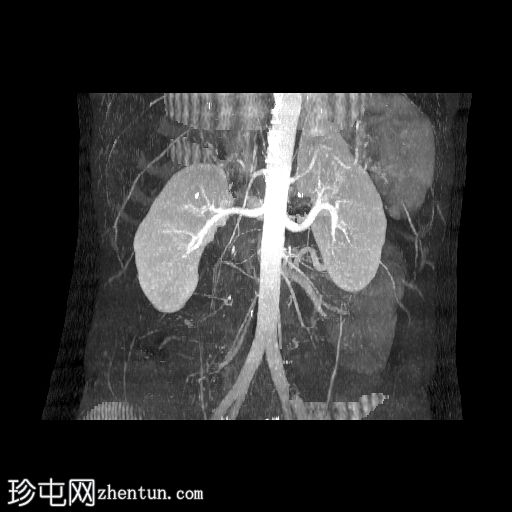

CT肾血管造影显示一条起源于左肾下段的副肾静脉,该静脉环绕主动脉走行,并接受来自腰静脉的属支,走行于主动脉后方,最终汇入下腔静脉。

本病例展示了一条环绕主动脉的副左肾静脉,其走行于主动脉后方并汇入下腔静脉,而右肾静脉解剖结构正常。

双侧肾动脉解剖结构正常,双侧肾动脉均起源于L2椎体水平的腹主动脉,管径正常,无狭窄、动脉瘤、夹层或副动脉。